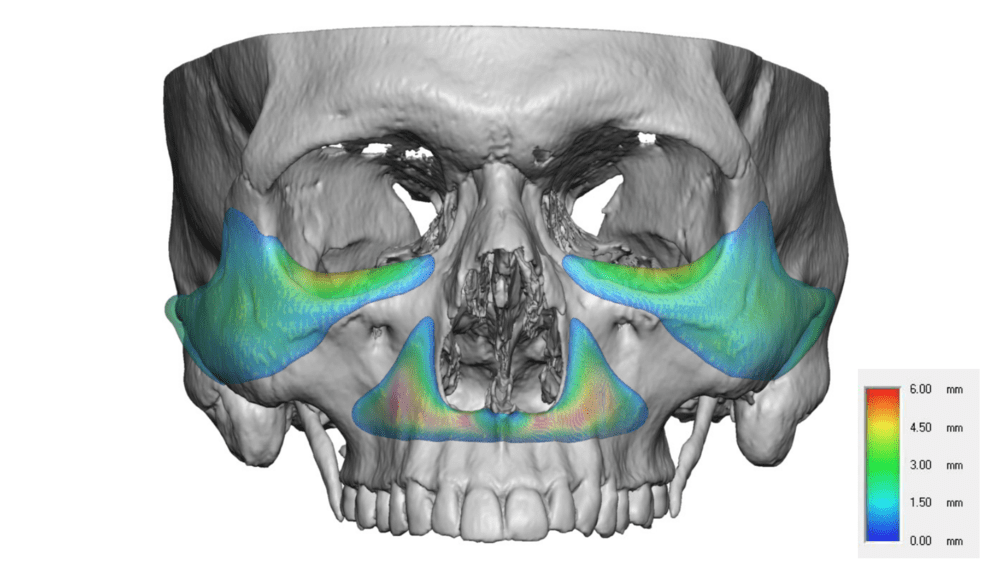

Notice the blue part added in the lf2 diagram.

Instead of doing the big lefort 3 cut, why cant we just add the cheekbone part to the lefort 2?

Instead of doing the big lefort 3 cut, why cant we just add the cheekbone part to the lefort 2?